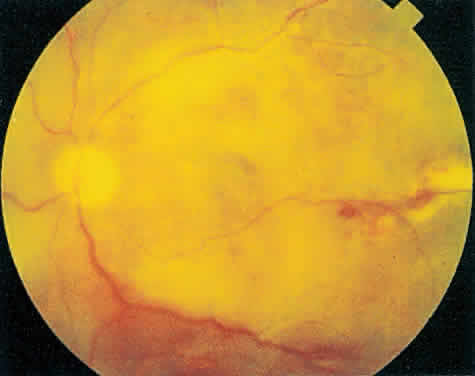

Over a course that usually spans weeks, infiltrates of CMV tend to assume two different patterns of clinical disease.11,12 The first pattern is called hemorrhagic and is characterized by broad geographic zones of retinal whitening. These large, geographic lesions are usually in close proximity to a major retinal blood vessel or the optic nerve. Satellite lesions are common. When the retinal necrosis associated with CMV retinitis becomes widespread, it is almost invariably associated with retinal hemorrhages. Although the border between necrotic and unaffected retina is sharply demarcated, the border itself appears irregular and jagged. Exudation into the retina or subretinal space may be seen, adding to the granular appearance of the retinitis. Juxtaposition of large zones of white, granular necrosis with those of red retinal hemorrhage has led this appearance of CMV retinitis to be described as either “pizza-pie” or “cheese and ketchup.” The retinal blood vessels, both arteries and veins, in the areas of necrosis commonly appear sheathed, secondary to a vasculitis. As a consequence, secondary retinal vascular occlusions, especially branch retinal vein obstructions, may occur in the course of CMV retinitis. Immune-mediated vascular damage may play a role in the vasculitis.12 Central healing of these lesions will occur as the infection progresses. Avasculitis resembling “frosted branch angiitis” hasbeen reported (Fig. 2).28 A second pattern of CMVretinitis has been labeled “granular” or “brushfireborder.” In this appearance, the focal granular infiltrates enlarge slowly across a line, leaving ever-increasing areas of destroyed retina and atrophic retinal pigment epithelium behind. Hemorrhages and vitreous cells are a less prominent feature. There appears to be direct cell-to-cell transfer of infected virions in this pattern of infection (Figs. 3 and 4). The brushfire border is commonly seen in CMV retinitis lesions anterior to the equator (Fig. 5). The significance, if any, of these two clinical patterns of CMV retinitis is not known, and, in some eyes, both patterns of disease can be seen simultaneously or in sequence. Progression of retinitis has been defined in clinical trials as movement of a lesion border at least 750 μm along a front that is 750 μm or more in length, development of a new CMV lesion in a previously involved eye or in the uninvolved fellow eye of a patient with baseline unilateral disease.29 Without treatment or improvement in the host's immune system, CMV retinitis is a relentless, slowly progressive infection resulting in blindness caused by total retinal necrosis, retinal detachment, or optic nerve involvement, in any combination.